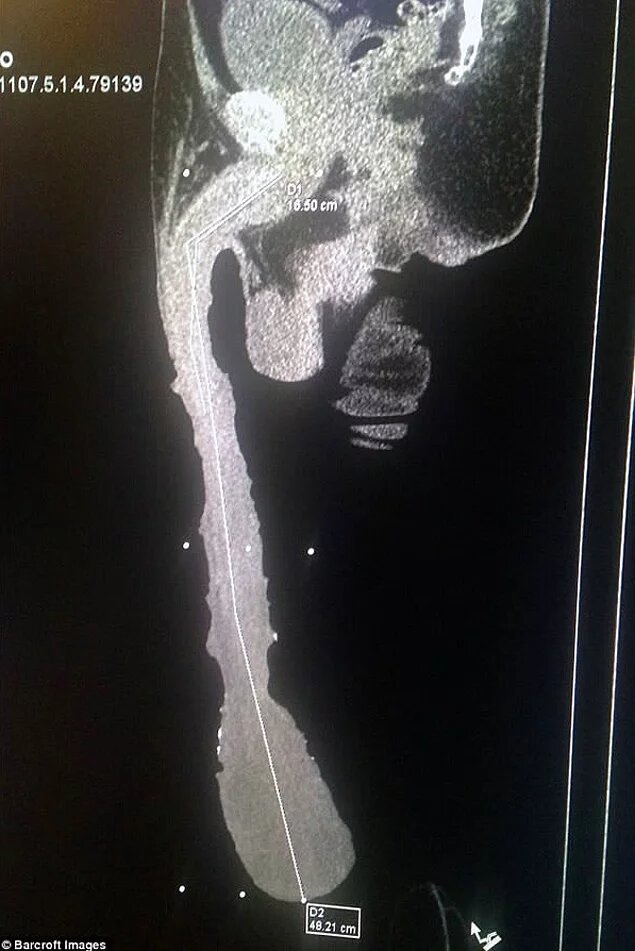

Длина полового члена Роберто составляет 48 см! Кабрера гордится этим, отмечая, что это достижение достойно Книги рекордов Гиннесса